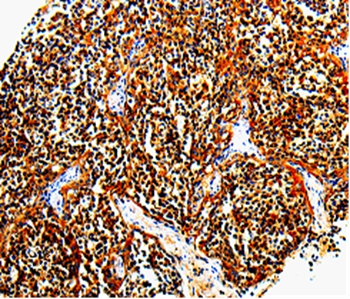

Immunohistochemical analysis of paraffin-embedded Human tonsil tissue using #35578 at dilution 1/10.

应用详情:Immunohistochemistry: 1:10-1:50